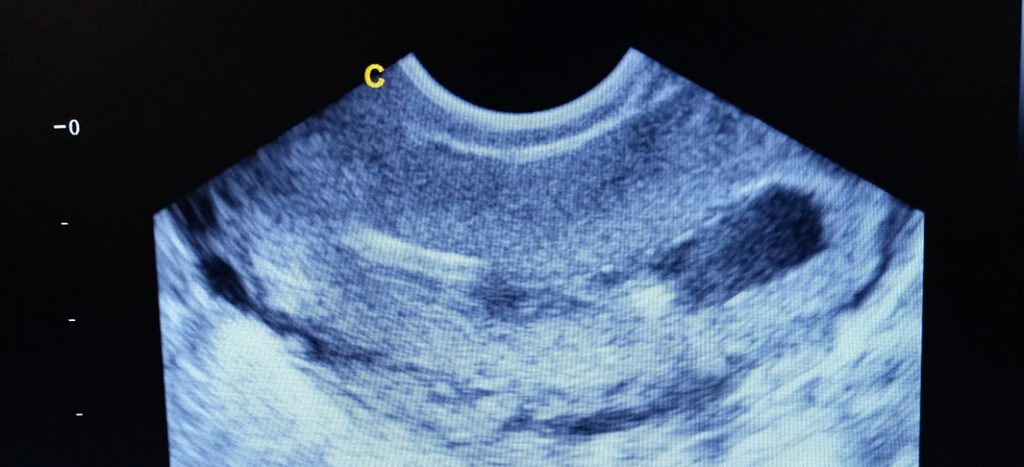

Endometrial polyps are common, benign (non-cancerous) growths on the lining of the uterus (endometrium). They can vary in size, shape and number (from a few millimetres to several centimetres) and may appear gradually or suddenly.

In Australia, the two most common methods are:

Often used as a first-line screening tool. However, polyps may be missed in up to half of cases, and it doesn’t allow for treatment.

A thin telescope inserted through the cervix into the uterus. This allows polyps to be diagnosed and removed at the same time.